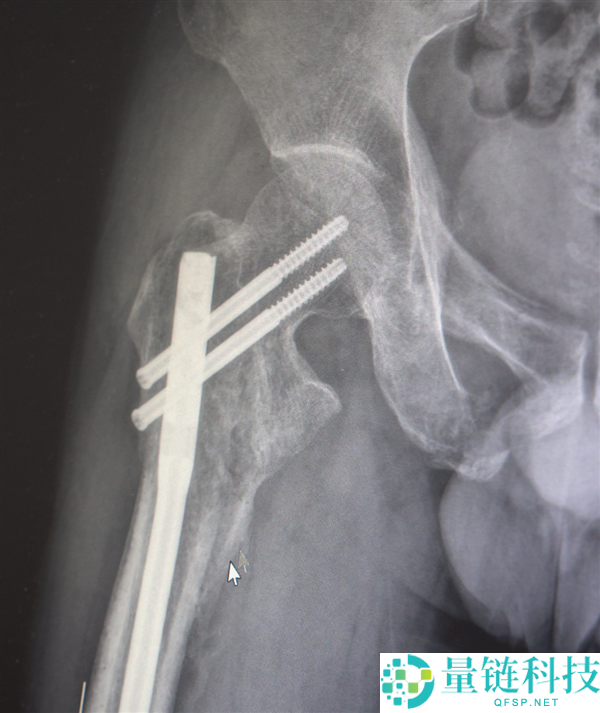

创伤性失血性休克、多发性肋骨骨折、肺部损伤、右侧肩胛骨粉碎骨折、右侧肱骨髁上开放粉碎性骨折、右股骨粗隆及股骨干粉碎性骨折、骨盆粉碎性骨折、腰椎横突多发骨折、腰骶柱神经损伤、臂丛神经损伤、胸腔积液、腹腔积液等。

经医生检查,张先生全身共有六处较大骨折部位,多为严重粉碎性骨折,全身骨折碎块达30多块!

部分手术后拍摄的影像